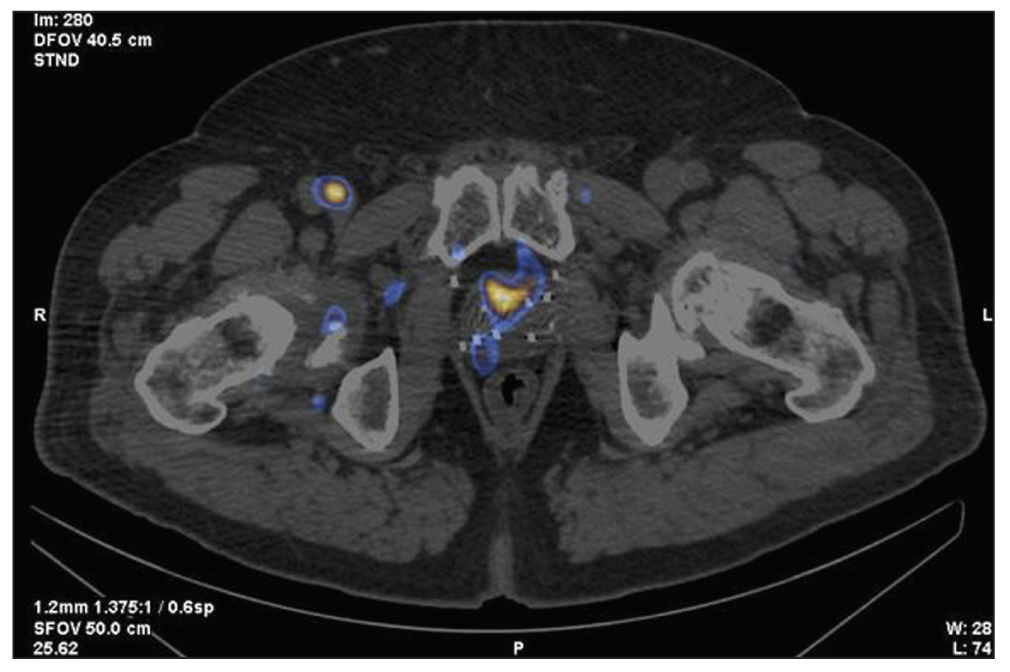

Patient Z., 79 years old, was admitted with diffuse prostatic hyperplasia. PSA level was 4.5 ng/mL. No abnormal lesions were found in the prostate tissue using ultrasound, TRUS, and contrast-enhanced MRI. SPECT/CT with 99mTc-HYNIC-PSMA revealed 15-mm3 sites of RP accumulation in the prostate tissue (Figure 3). Because rectal amputation made US-guided prostate biopsy impossible, a targeted CT-guided biopsy was performed pararectally. A morphological diagnosis was adenocarcinoma, Gleason 6 (3 + 3).

Fig. 3. Patient Z., 7 years old, SPECT/CT with 99mTc-HYNIC-PSMA: Sites of radiopharmaceutical accumulation in transitory zones of both lobes at the border of the middle third and the apex of the prostate gland.

In this case, two problems were revealed: an unknown cause of increased PSA over time and the inability to perform a targeted prostate carcinoma biopsy under US guide. Both problems were successfully resolved using hybrid SPECT/CT with 99mTc-HYNIC-PSMA followed by CT-guided RP accumulation site biopsy, and precision brachytherapy was performed with a smaller number of 125I microsources due to the SPECT/CT pattern.